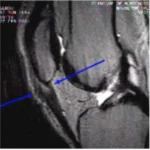

Lesão do Ligamento Cruzado Anterior (LCA) do Joelho

O ligamento cruzado anterior (LCA) é o principal estabilizador do joelho, impedindo o deslocamento anterior da tíbia em relação ao fêmur. Pacientes com lesão do LCA frequentemente relatam um episódio de entorse ou trauma no joelho, seguido de inchaço, dor e, posteriormente, sensação de falseio.

A instabilidade causada por essa lesão pode levar a lesões degenerativas da cartilagem articular a partir de 6 meses. Após 5 anos de lesão, 50% dos pacientes desenvolvem artrose no joelho, e após 10 anos, 75% apresentam esse quadro.

Em 50% dos casos, pacientes com lesão do LCA também possuem lesões meniscais associadas, sendo mandatório investigar essas ocorrências. O exame clínico, com testes como Lachmann e Pivot Shift, possui alta acurácia no diagnóstico.